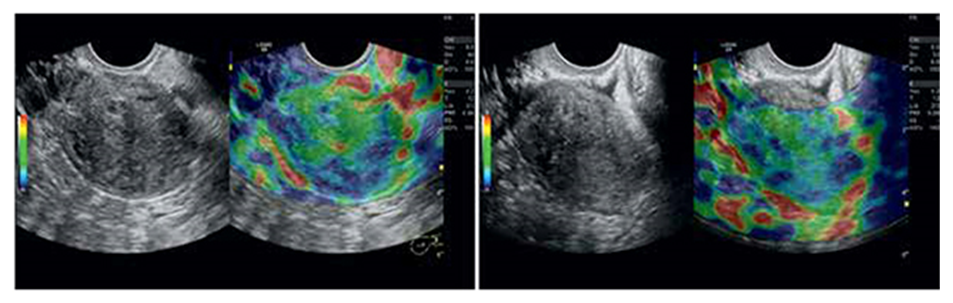

Signs of stage I adenomyosis:• formation of small (approximately 1 millimeter in diameter) anechoic cylindrical structures originating from the endometrium in a direction toward the myometrium;• appearance of small hypo- and anechoic connections in the basal layer of the endometrium, convex or rounded in shape, approximately 1–2 millimeters in diameter;• discontinuous thickness of the basal layer of the endometrium;• serration or unevenness of the base layer of the endometrium;• detection of "bittenness" or localized damage to the endometrium;• the appearance in the myometrium directly adjacent to the uterine cavity of single zones of high echogenicity up to 3 millimeters wide.Signs of grade II adenomyosis:• an increase in the thickness of the uterine walls exceeding the upper limit of normal;• a thickening of one uterine wall compared to the other by 0.4 cm or more;• the appearance in the myometrium directly adjacent to the uterine cavity of zones of increased heterogeneous echogenicity of varying thickness;• the appearance in the zone of increased echogenicity of small rounded anechoic formations 2-5 mm in diameter, as well as fluid cavities of various shapes and sizes containing a fine suspension (blood), and sometimes dense inclusions of low echogenicity (blood clots);• ultrasound signs observed in stage I disease (they are also characteristic of all other manifestations of internal endometriosis).Uterine thickness in stage II adenomyosis is increased in approximately half of patients.Signs of stage III adenomyosis revealed on scans:• uterine enlargement in the main anteroposterior volume;• preferential increase in the thickness of one of the uterine walls;• the appearance of an area of high mixed echogenicity in the myometrium, occupying more than fifty percent of the uterine wall thickness;• the detection of anechoic connections with a diameter of 2–6 mm or fluid cavities of various shapes and volumes, including a finely dispersed suspension, in the echogenic area;• the appearance of numerous adjacent stripes of typical low echogenicity, directed vertically to the plane of recognition, in the painful area. • detection in the area of the leading front of recognition of an area of high echogenicity, and also an anechoic area in the area of the distant front;Ultrasound elastography revealed marked diffuse heterogeneity of myometrial staining in 72% of patients with diffuse adenomyosis. Mixed mosaic staining was observed in 61% of cases (Fig. 2), shades of blue in 33%, and shades of red in 6%. | Figure 2. Ultrasound elastography of the uterus, diffuse and nodular types of adenomyosis |